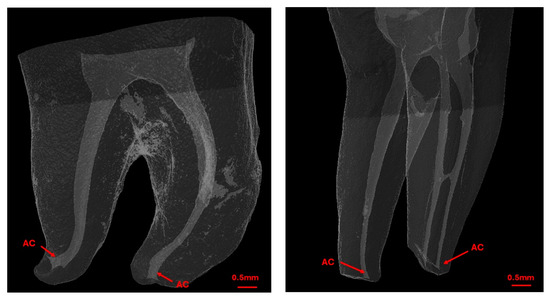

Background: Determining the correct apical limit for root canal treatment is essential for its success. This study evaluates the accuracy of three electronic apex locators (EALs) in locating the apical constriction (AC) in molar canals. Methods: Forty extracted human mandibular molars were scanned using micro-CT, and endodontic access cavities were created. Teeth were mounted in alginate, and three EALs—Root ZX-mini, Root ZX-II, and Sirona integrated apex locator—were used to measure the canal working length in dry canals and with EDTA gel. Micro-CT scans were performed with files in place, and the distance from the AC was calculated. Measurements within 0.1–0.5 mm were categorized as ‘close’. Those extending beyond towards the major foramen were categorized as ‘beyond’, otherwise they were classified as ‘far’. Data analysis was conducted with a level of significance set at 5%. Results: Most readings for all EALs were in the ‘close’ category, with significant differences between devices (p < 0.0001). Root ZX-mini and Root ZX-II had 74.4% and 72.5% ‘close’ readings, respectively, versus 51% for Sirona integrated. Accuracy did not differ significantly between dry and EDTA-treated canals (p = 0.306). All EALs demonstrated excellent operator reliability (ICC 0.996–1.00). Conclusions: All EALs accurately determined AC, unaffected by lubricants. However, Root ZX-mini and Root ZX-II outperformed Sirona integrated. All EALs showed consistent reliability. Full article